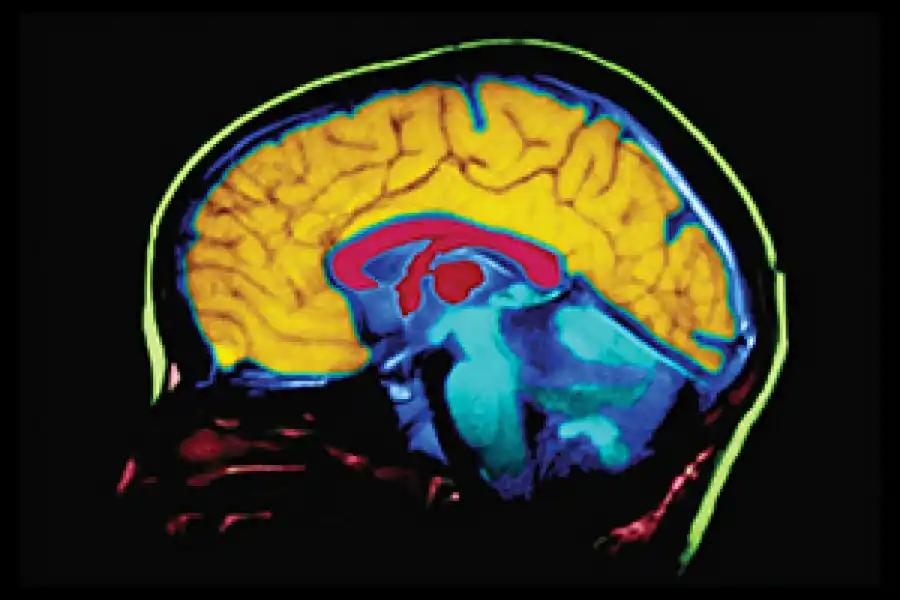

Los científicos plantean la hipótesis de que el uso a largo plazo de estos antiinflamatorios puede reducir la acumulación de placas beta amiloide en el cerebro, que siguen siendo un sello distintivo de la demencia y la enfermedad de Alzheimer. Sin embargo, los resultados excluyeron a las personas que eran portadoras del gen APOE-ε4, un factor de riesgo conocido para el Alzheimer.